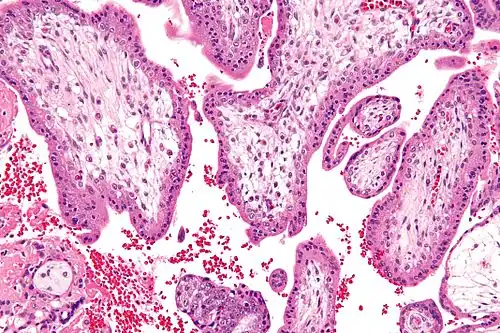

![]() Micrograph showing chorionic villi—the tissue that is collected in CVS. H&E stain. | |